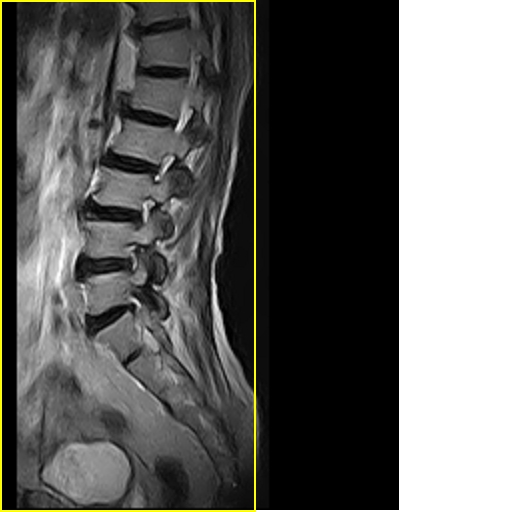

标题: MRI0859:[原创]腰椎,男,78岁,右下肢跛行两月 [打印本页]

男,78岁,右下肢跛行两月.

右侧黄韧带肥厚或钙化,压迫马尾神经所致。必要时行ct扫描。

腰间盘膨出、黄韧带肥厚、可疑先天性腰椎管狭窄。

退行性病变:增生、椎间盘变性、膨出[l4-5、l5-s1 椎间盘膨出]

退行性骨关节病:增生、椎间盘变性、膨出..黄韧带肥厚.